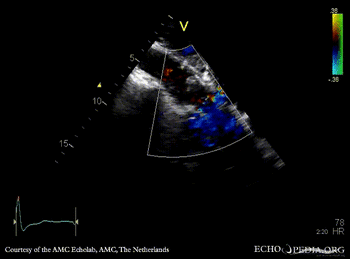

PSAX: stenosis of aortic valve PLAX with Color Doppler: high velocity transaortic flow, mild aortic regurgitation